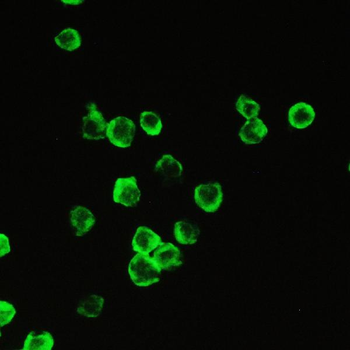

100 μgFKBP52 Antibody: Biotin [orb147211]

ELISA, ICC, IF, IHC, WB

Canine, Hamster, Human, Mouse, Rat

Mouse

Monoclonal

Biotin

100 μg